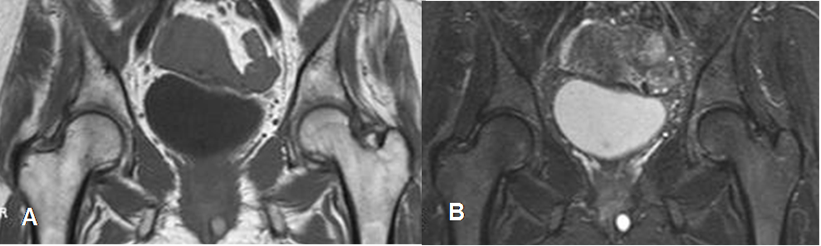

Fig 88 B. Osteoporosis transitoria.

A: RM coronal en T1 y B: RM coronal en STIR. Igual paciente anterior. Normalización de los cambios, después de 3 meses.